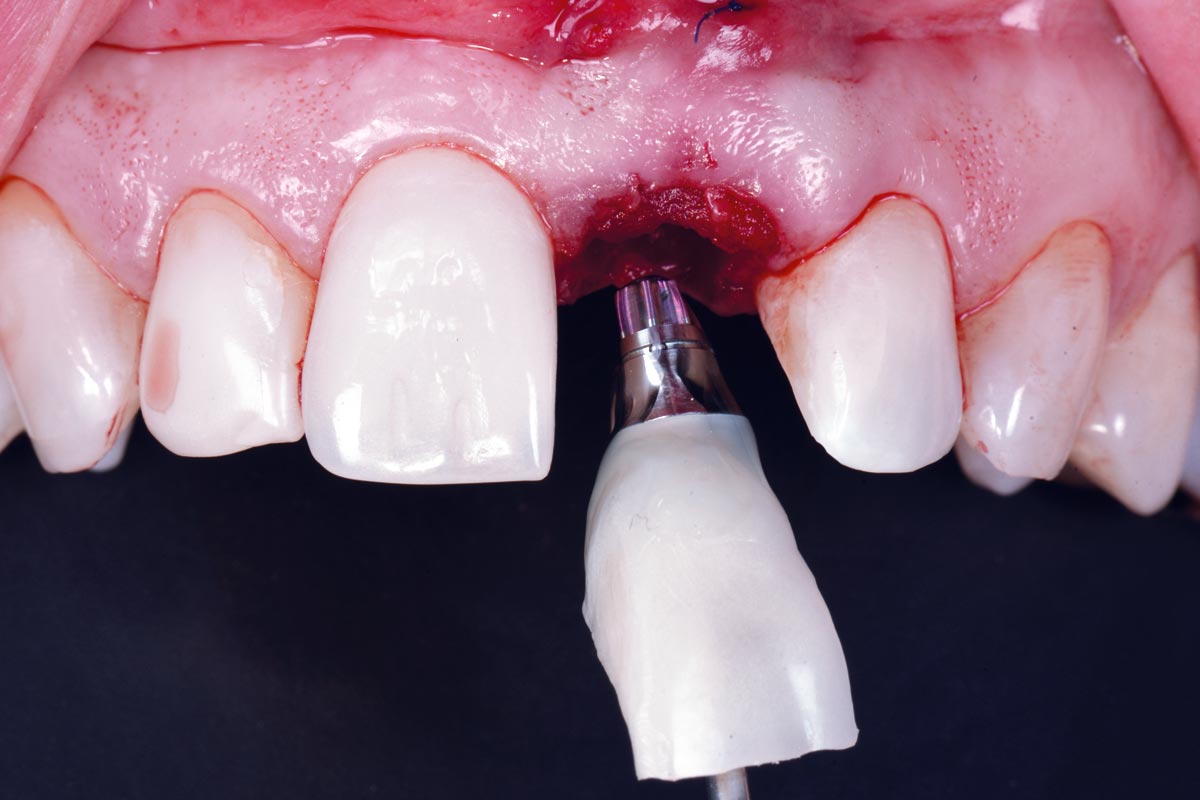

cerabone® and mucoderm® for immediate implantation in the aesthetic area - Dr. D. Robles

Initial clinical situation - Central incisors with dental destruction and periapical pathology